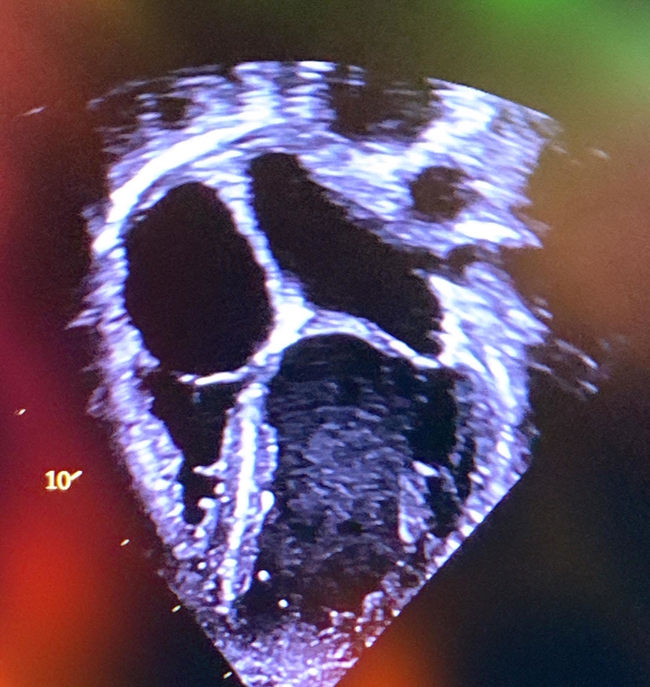

Innan min första operation så valde jag att komma ner en vecka före operations-dagen för att bidra till en studie/forsking med mitt hjärta för framtida hopp att kunna hjälpa andras barnhjärtan i tid.